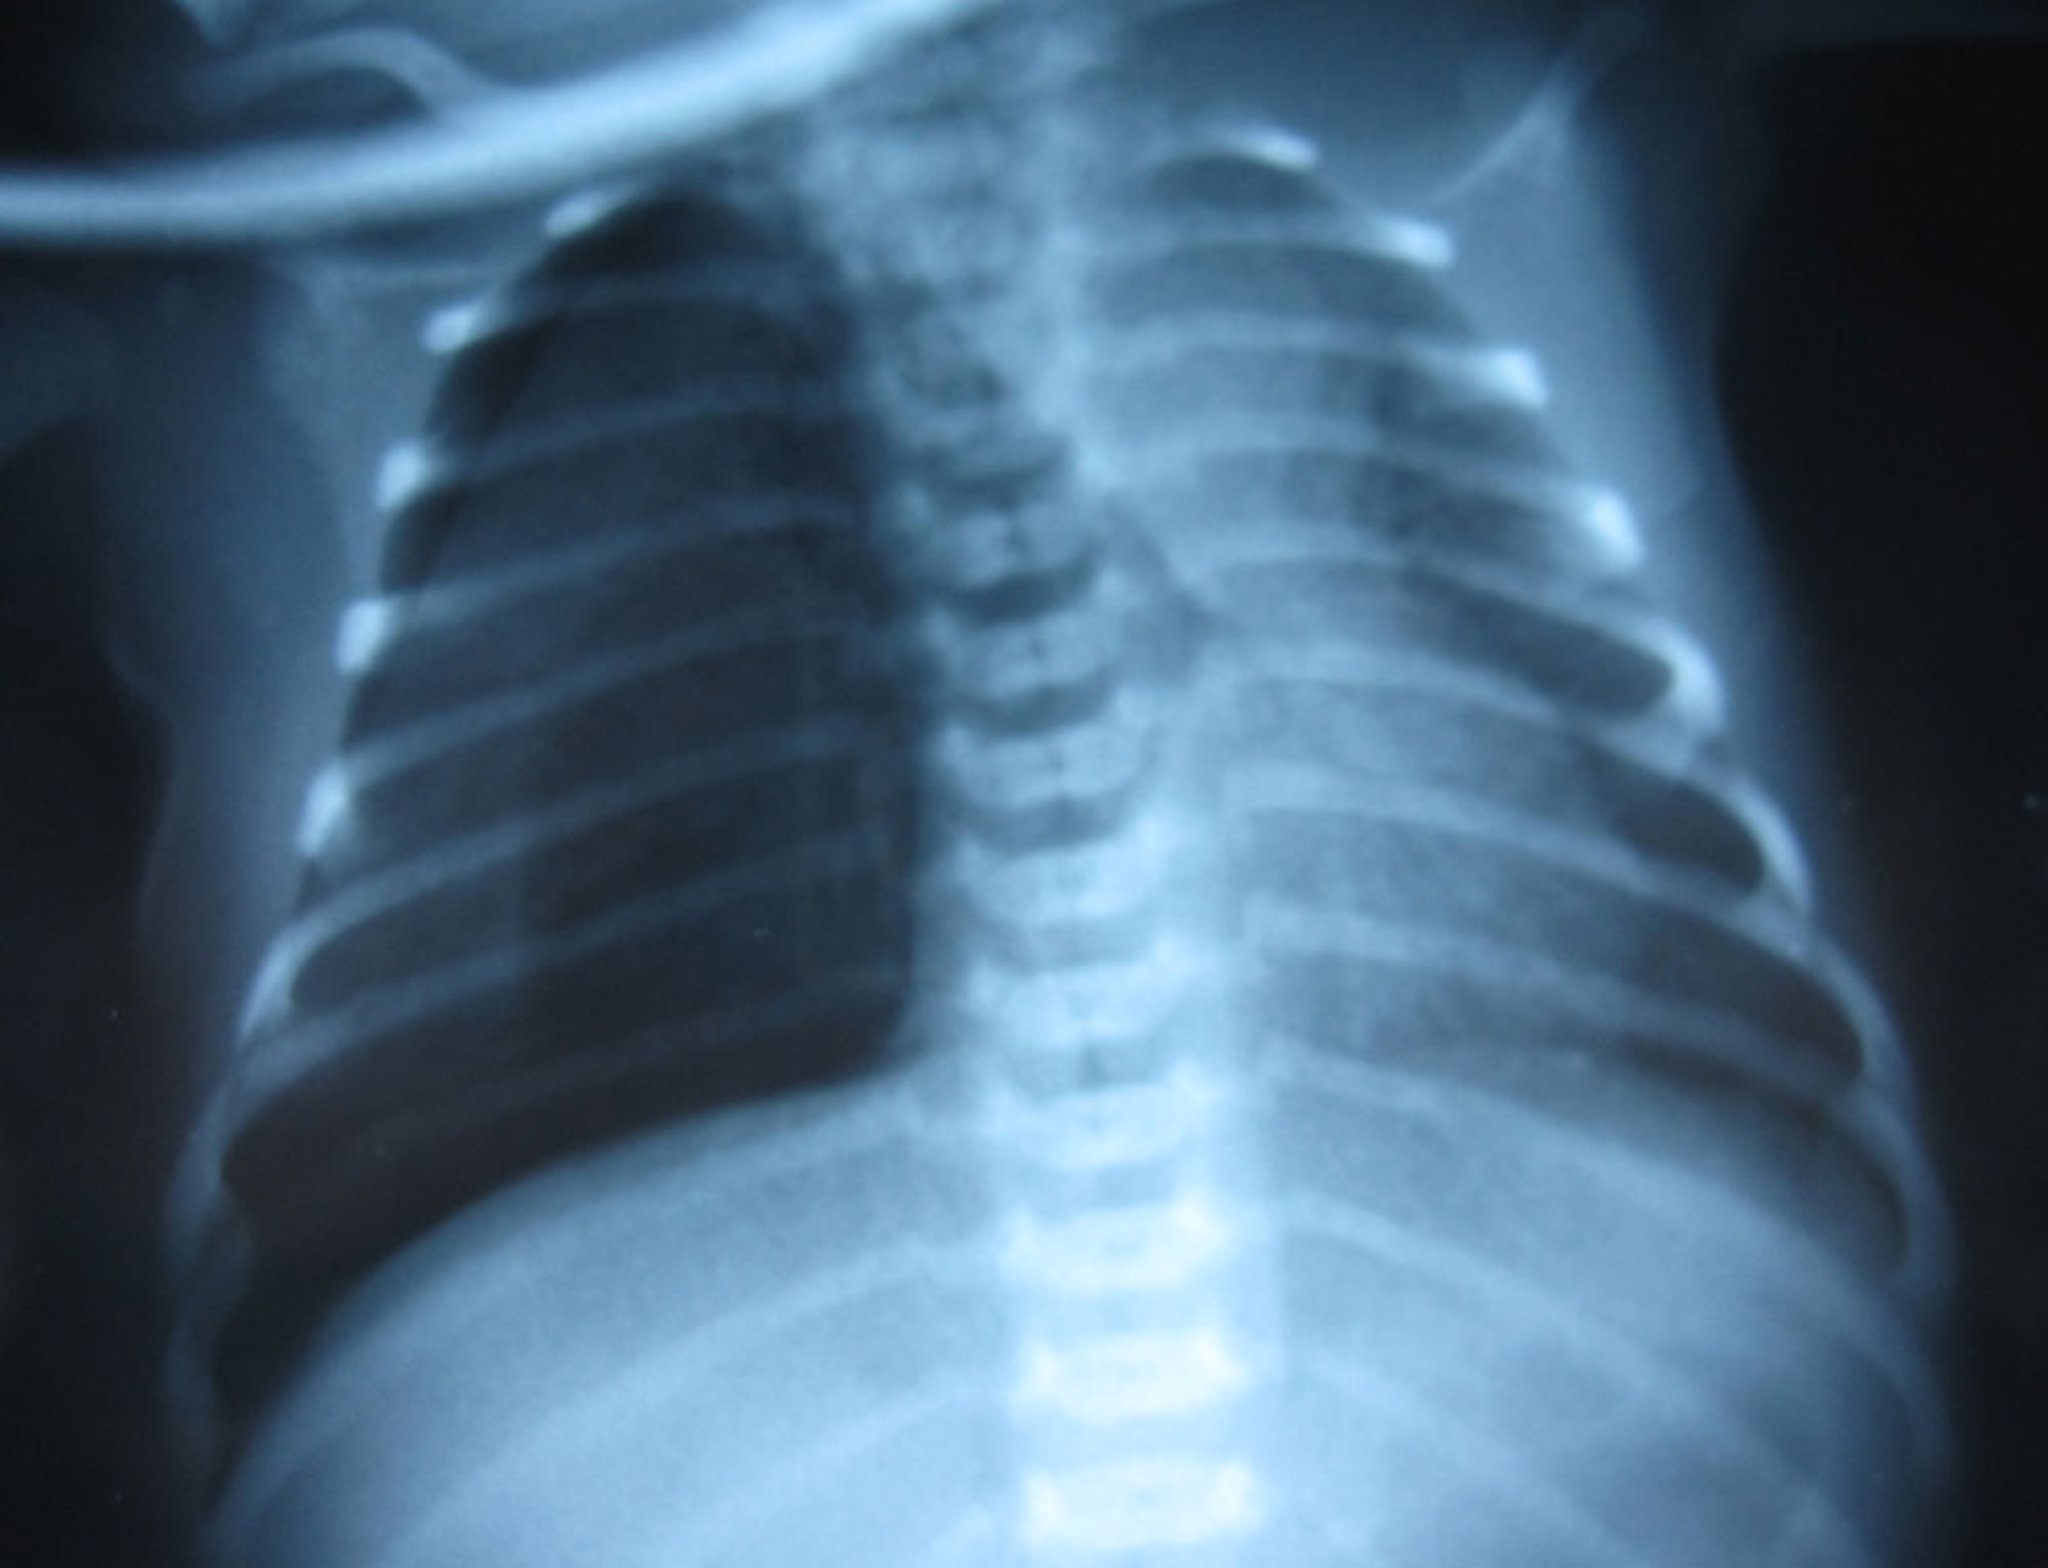

新生儿右侧张力性气胸,可见肺边缘,右侧肺血管标记极少。张力性气胸是一种临床诊断,而不是影像学诊断,但在本图中,纵隔明显向左移位高度提示张力性气胸。

Image courtesy of Arcangela Balest, MD.